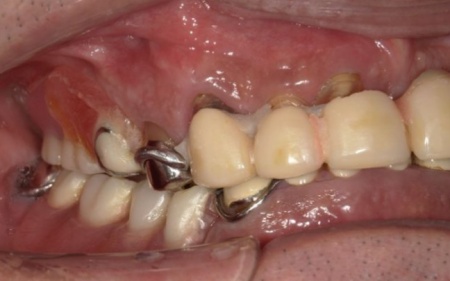

70代男性 温存が難しい歯を抜きインプラントオーバーデンチャーで全体的な噛み合わせを改善した症例

「ブリッジが壊れてしまってちゃんと噛めなくなった。これを機に、口腔内全体を治療したい」とご相談いただきました。

拝見したところ、すでに複数の歯が欠損しており、上下顎には入れ歯が装着されていました。

上前歯は、装着していたブリッジ(複数の人工歯を連結した被せ物)が外れてしまっているため、食事や会話に大きな支障をきたしています。

残っている歯についても、長期間の負担により状態が悪く温存が困難な歯や、細菌感染した神経を取り除いてから薬を詰める根管治療が必要な歯がありました。

このような状態では、ブリッジの壊れた部分だけを直す応急的な治療では根本的な解決にはならず、むしろ残っている歯にさらに大きな負担をかけてしまうおそれがあります。

また、従来の入れ歯は残っている歯にバネをかけて支えるため、その歯に過度な力がかかり続け、将来的にはその歯も失ってしまうリスクが高い状況です。